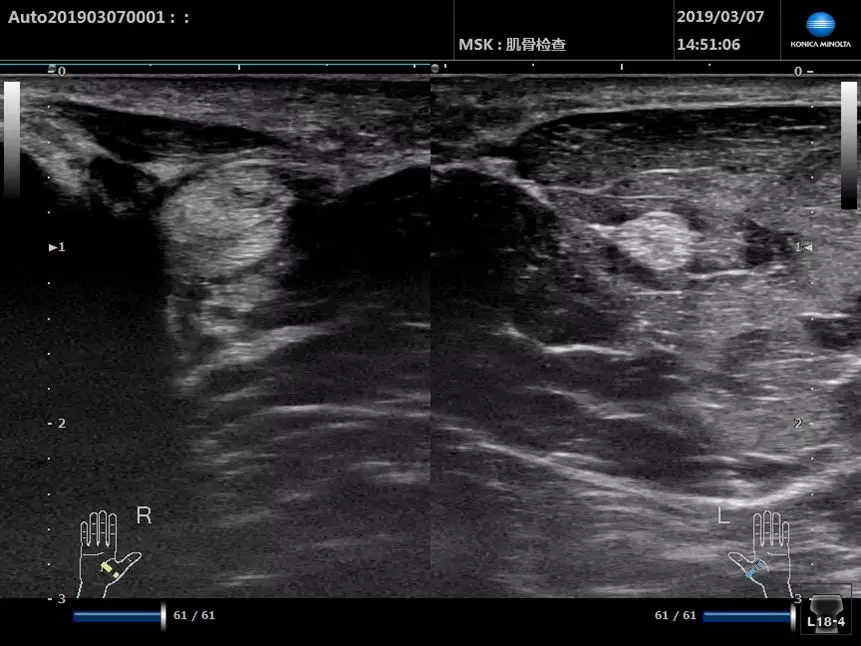

超聲下的姆長屈肌腱(短軸)

■ 患者,中年女性,左圖為患側,右圖為健側,患側肌腱明顯增粗